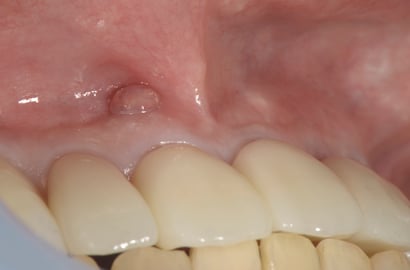

前歯の歯肉に近い場所に”おでき”のようなものができています。これを瘻孔(ろうこう、サイナス・トラクト)といいます。

歯の根の”破折”や”ヒビ”がある時にもできますが、状態が違います。ここでの瘻孔は、神経がない歯の根の先に炎症が生じ(根尖病巣)、それが歯の根を支える(歯槽骨)と歯肉を経由(瘻管形成)して、出口がこの瘻孔となります。当院では、根尖病巣が原因で生じた瘻孔は、1回の治療後、約3日〜1週間で消失させることが可能です。

この症例では、治療後3日で瘻孔は消失しました。

歯の神経を除去する治療をしていない歯であっても、何らかの原因で歯髄が死んでしまい、同様に瘻孔形成をすることもあります。